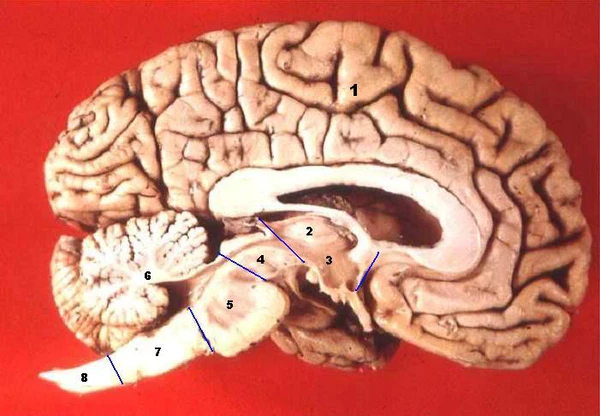

В головном мозге различают несколько отделов: продолговатый мозг; задний, включающий в себя мост, мозжечок и эпифиз; средний; промежуточный; и передний мозг, представленный большими полушариями.

Продолговатый мозг — задний отдел головного мозга, непосредственное продолжение спинного мозга. Происходит из ромбовидного мозга и входит в ствол головного мозга. Регулирует такие основные процессы жизнедеятельности, как дыхание и кровообращение, поэтому в случае повреждения продолговатого мозга мгновенно наступает смерть. Также регулирует сосудистый тонус. Является местом, где находятся центры чихания, кашля и рвоты.

Задний мозг — это вторичный мозговой пузырь, развивающийся из передней части эмбрионального ромбовидного мозга. В дальнейшем задний мозг даёт начало мосту мозга и мозжечку.

Мост — отдел ствола головного мозга, является вместе с мозжечком частью заднего мозга. Основной его функцией является передача информации из спинного мозга в отделы головного. Через мост проходят все восходящие и нисходящие пути, связывающие передний мозг со спинным мозгом, с мозжечком и другими структурами ствола.

Мозжечок — отдел головного мозга позвоночных, у человека расположенный позади продолговатого мозга и моста, под затылочными долями полушарий головного мозга. Главными функциями мозжечка являются:

Средний мозг — отдел головного мозга, развивающийся из среднего из трёх первичных мозговых пузырей эмбриона. Ответствен за осуществление многих важных физиологических функций, таких, как зрение, слух, контроль движений, регуляция циклов сна и бодрствования, общего уровня возбуждения ЦНС, концентрации внимания, ориентировочные, защитные и оборонительные рефлексы, регуляция болевой чувствительности, репродуктивного поведения, температуры тела.

Промежуточный мозг — отдел головного мозга хордовых животных, который образуется в процессе эмбрионального развития из задней части зародышевого переднего мозга. Состоит из таких частей, как гипоталамус, таламус и третий желудочек. Большинство его функций относится к нейрогуморальной регуляции, а также регуляции деятельности внутренних органов, желёз внутренней секреции и вегетативной нервной системы. В нём находятся центры сна и бодрствования, голода, насыщения и жажды, терморегуляции.

Конечный мозг — самый передний отдел головного мозга. Состоит из двух полушарий большого мозга (покрытых корой), мозолистого тела, полосатого тела и обонятельного мозга. Является наиболее крупным отделом головного мозга. Это также самая развитая структура, покрывающая собой все отделы головного мозга.